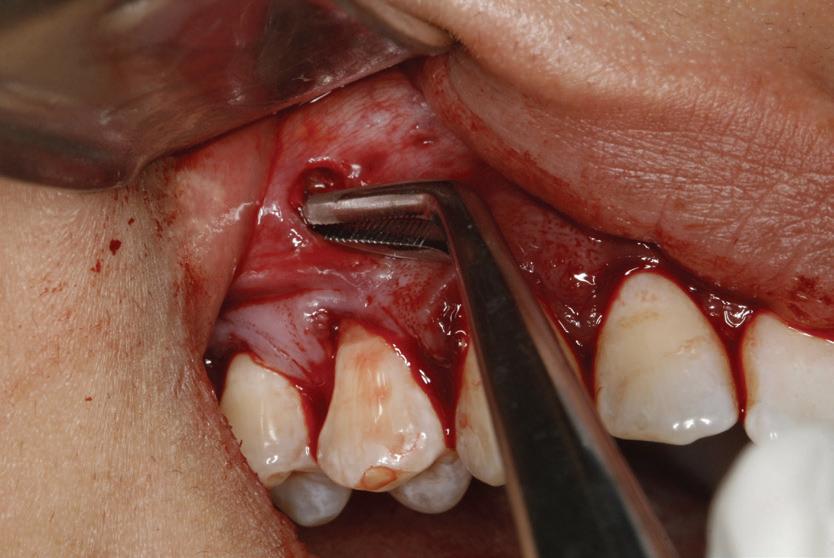

Lamboul repoziționat apical

Această tehnică este o opțiune atunci când nu există suficient țesut gingival keratinizat și este preferată atunci când caninul impactat este situat mezial față de incisivul lateral. Lamboul trebuie fixat și adaptat la dinte. Dezavantajele includ riscul de recesie și marginea gingivală neregulată, alături de necesitatea unei intervenții chirurgicale osoase extinse. Se efectuează incizii verticale, iar lamboul este deplasat într-o direcție laterală sau apicală. Se recomandă un design al lamboului în care baza și zona coronară sunt fie la aceeași lățime, fie mai înguste la bază, cu o grosime de 4-5 mm, astfel încât lamboul să fie suficient de lat meziodistal, extinzându-se cu 1,5 mm dincolo de unghiul dintelui (fig. 6, 7).

Osul acoperitor trebuie îndepărtat cu chiuretă sau freză diamantată pentru a expune porțiunea liberă a coroanei. Lamboul se poziționează apoi la CEJ și se fixează cu suturi periostale pentru o stabilitate mai mare. În funcție de gradul de impactare a caninului, se poate plasa un pansament parodontal, astfel încât țesutul să nu se închidă. Bracketul este plasat fie în momentul procedurii, fie la 10 zile postoperator. Dacă respectivul canin este situat prea apical, se preferă tehnica închi-